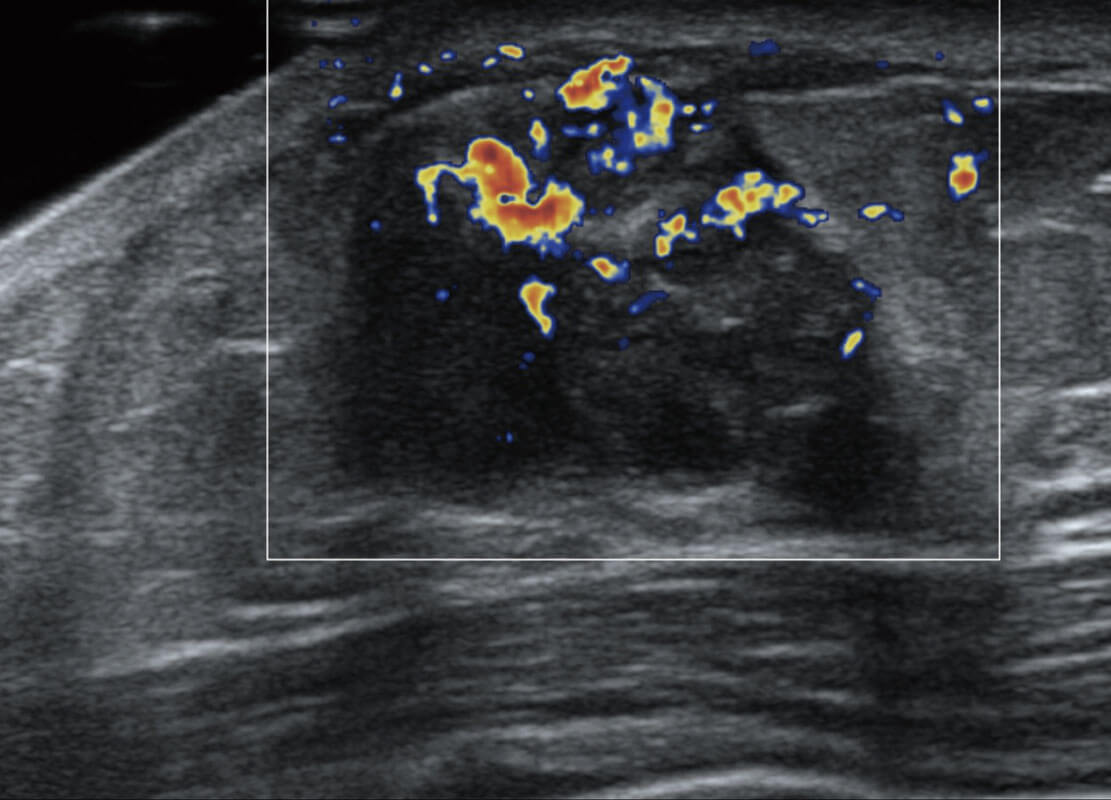

P60搭載寬頻帶線陣探頭、寬景成像、彈性成像技術(shù),為您提供乳腺應(yīng)用方案。P60支持高頻相控陣探頭、線陣探頭、腹部高頻探頭、腹部微凸探頭等,豐富的探頭群搭載敏感的彩色血流成像,適用于新生兒多種臟器檢測(cè)要求,滿足新生兒篩查需求。

乳腺導(dǎo)管癌

乳腺癌顯微血流